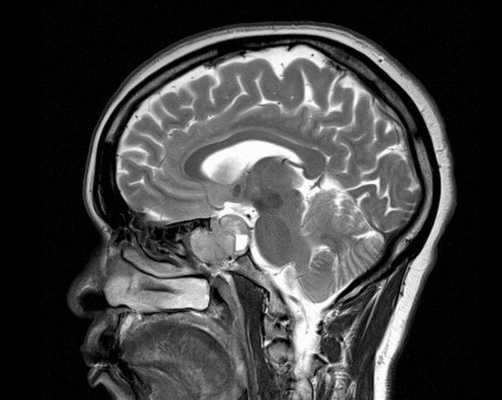

Гипофиз на снимке МРТ

Электромагнитный импульс вызывает смещение атомов водорода в диполях воды. Колебания заряженных частиц регистрируют при помощи чувствительных детекторов, затем информацию обрабатывают и преобразуют в серию фотографий тонких срезов исследуемого участка. Послойные снимки транслируют на монитор компьютера для детального изучения врачом-рентгенологом.

В норме воронка гипофиза должна располагаться на срединной линии, а сама железа - иметь однородную структуру и близкую к прямоугольной форму. Его нижний край должен напоминать изгиб турецкого седла, а верхний может быть выпуклым, прямым или вогнутым. На фронтальной проекции его части должны быть симметричны, но легкие отклонения не считаются патологией.

МРТ гипофиза в норме